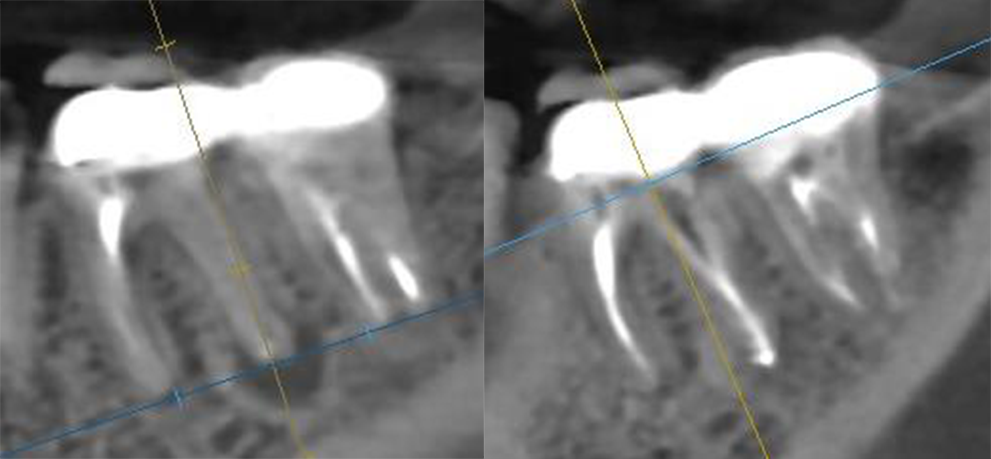

Лечение периодонтита до (слева) и после (справа)